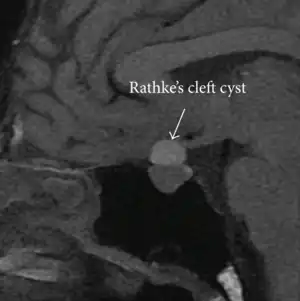

Rathke's cleft cyst

Rathke's cleft cyst in a 53-year-old man with a pituitary adenoma and acromegaly

A Rathke's cleft cyst is a benign growth on the pituitary gland in the brain, specifically a mucin-filled[1] cyst in the posterior portion of the anterior pituitary gland.[2][3] It occurs when the Rathke's pouch does not develop properly and ranges in size from 2 to 40 mm in diameter.[3]